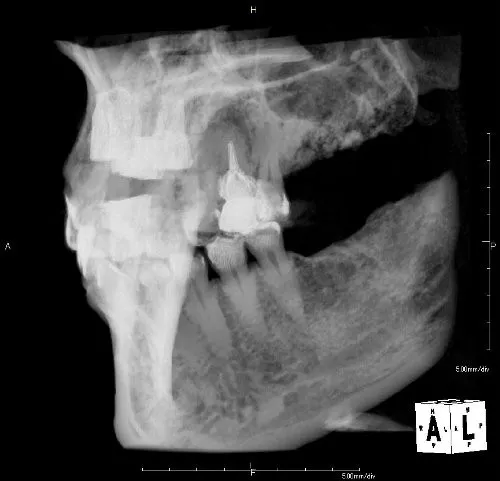

症例③

| 主訴 | 他院にて抜歯後、歯を入れたい |

| 診断名 | 歯根破折 |

| 年齢 | 46歳 |

治療に用いた装置(治療法) | 骨造成・インプラント |

| 部位 | 右上1 |

| 治療期間 | 8か月 |

| 治療費用 | 造成:55,000円 インプラント:462,000円 |

| リスク・副作用(治療に関する) | 腫服、しびれ |